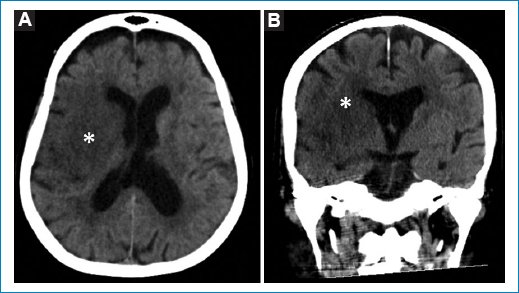

Respecto a los cinco pacientes con hallazgos patológicos agudos en la TCC, cuyas características demográficas y clínicas se describen en la tabla 2, se reconocieron un ACV isquémico agudo en el territorio de la arteria cerebral media derecha (Fig. 1), un edema cerebral difuso por encefalitis (Fig. 2), una encefalopatía necrotizante aguda (Fig. 3) y dos hematomas intracraneales intraaxiales, de los cuales uno en se ubicó en los núcleos de la base del hemisferio cerebral izquierdo y el otro en el lóbulo parietal derecho (Fig. 4). Todos ellos correspondieron a cuadros de dengue grave.

Figura 2. TCC de un paciente de 25 años con edema cerebral difuso por encefalitis. Obsérvense la obliteración del espacio subaracnoideo (asteriscos), la reducción en el tamaño de los ventrículos laterales (flecha) y el colapso del cuarto ventrículo (flecha punteada). Imágenes axial (A) y sagital (B).